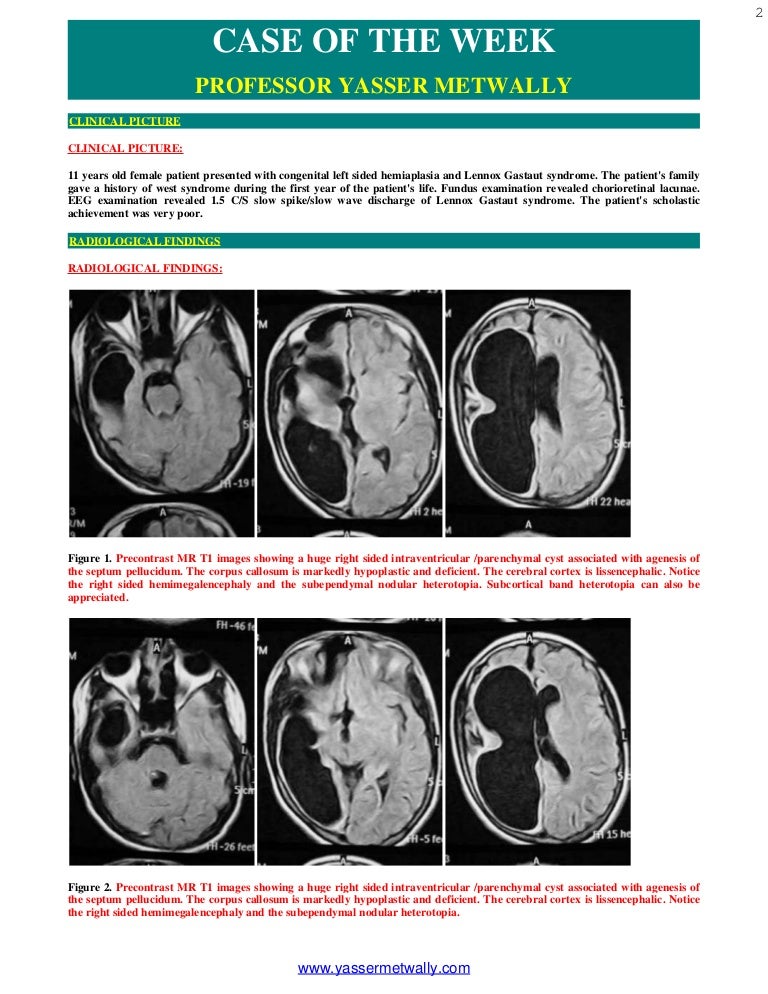

Case Of The Week Cases Presented With Cortical Dysplasia